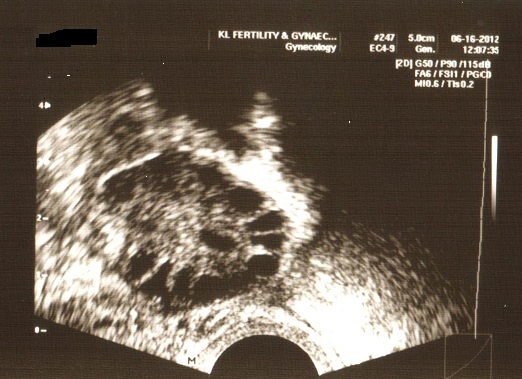

Your fertility specialist will start with an ultrasound scan of the pelvis to visualize the uterus and ovaries. This scan is usually done during your menstruation. Any abnormalities of these organs will easily be seen and if relevant, be acted upon. Your fertility specialist will visualize your ovaries to count the number of follicles present in the ovaries. Along with a blood test (which includes hormonal levels), these tests aim to assess your ovarian reserve, a term used to describe your fertility potential. A fertile woman generally has a good numbers of follicles in her ovaries and the number declines with age. The commonest hormone measured is called Follicle Stimulating Hormone (FSH). A high level of FSH indicates that the eggs are few and therefore a reduction in fertility.

An ultrasound scan to visualize the ovaries and count the number of follicles

Subsequently, another ultrasound scan around the time of ovulation may be performed to assess the receptivity of the lining of the uterus (endometrium). This test is important to exclude any problems that may interfere with the implantation of the embryos e.g. polyps or fibroids, which in turn leads to subfertility.

An ultrasound scan to visualize the lining of the endometrium